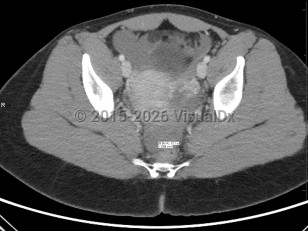

Ectopic pregnancies are, by definition, nonviable. If left untreated, they may cause their containing structure (eg, fallopian tube, cornua, scar) to rupture, leading to acute blood loss and subsequent morbidity and possibly death. Black women are nearly 7 times as likely as White women to die from the condition due to health disparities and access to care. Improved technology (biochemical markers, ultrasonography, etc) has enabled health care practitioners to identify a majority of ectopic pregnancies before rupture to reduce associated morbidity and mortality.

Ectopic pregnancies are found in reproductive-age patients. Risk factors include prior ectopic pregnancy, history of endometriosis or tubal infection (pelvic inflammatory disease), pregnancy occurring in the setting of current use of a progesterone intrauterine device (IUD), history of tubal surgery, advanced maternal age (aged 35 years or older at time of due date), and tobacco use. It is also important to note that over 50% of all patients diagnosed with an ectopic pregnancy have no known risk factors.